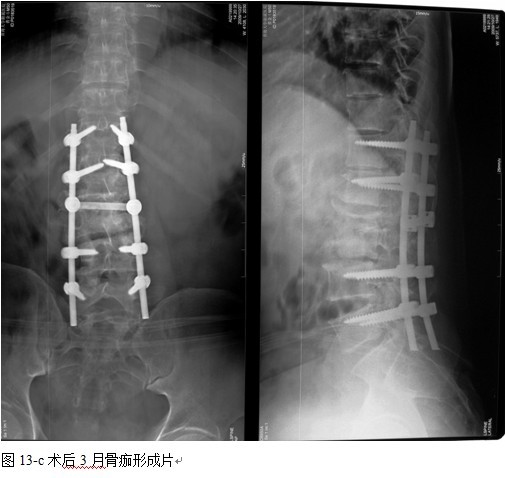

本组手术用时间3~4h , 平均3.5h 。术中出血300~500ml , 平均约350ml 。术后症状完全缓解,无神经功能障碍加重等并发症,1例营养差的老年患者伤口出现窦道,1例因肝功能差,术后未口服抗痨药,伤口出现窦道,经换药后二期愈合,其余病例伤口均一期愈合。马尾神经受损的患者术后基本恢复正常。术后一周后凸角平均 5.4°后凸畸形平均矫正90%以上, 最终后凸角平均8.3°,后凸角度平均丢失4.2°。随访3个月有87%(40/46)有骨痂形成,6个月91.3%(42/46)明显骨性愈合(见图),其余4例9-12个月内愈合,随访时间3-32个月,平均11个月,46例患者中2例在术后2个月和3个月时背部形成脓肿,换药后治愈。2例出院1月后并发结核性脑膜炎,治疗后好转。1例因椎弓根钉偏外,刺激神经根,5个月后从侧方脱出,疼痛加重,因前后路植骨完全愈合,取出后症状完全缓解。

中国学者金大地[22]等采用一期前路病灶清除植骨前路钢板固定治疗腰椎结核,平均18°的后凸畸形得以矫正,Mukhtar[23] AM等采用前路病灶清除植骨分期或同期后路固定治疗腰椎结核22例,术后后凸畸形矫正度数平均为27°。从我们的随访结果看,术后后凸畸形平均矫正度数为26.9°,后凸畸形平均矫正90%以上, 6个月-49个月后随访,后凸角度平均丢失4.2°。本术式也适用于结核所引起的弹性差的后凸畸形,对于病灶纤维化或骨化的非弹性后凸畸形,后路固定后,先行前路病灶、纤维化或骨化切除、松解,逐步刮除病灶、逐步撑开,达到畸形矫正和植骨的目的。